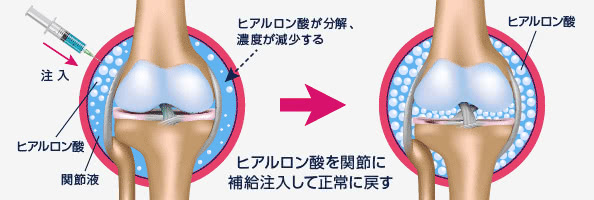

ヒアルロン酸注射

膝関節や肩関節にヒアルロン酸を注射する治療です。

再診時:注射代

3割負担:約700円

適応疾患

変形性膝関節症・肩関節周囲炎・関節リウマチに伴う膝関節痛

膝や肩の痛みを和らげる治療法として広く行われているのがヒアルロン酸注射です。

ヒアルロン酸は軟骨の保護や関節の潤滑の作用があり、1~2週間毎に5回行いその後は2~4週毎になります。

ヒアルロン酸の関節への注入で痛みの緩和や関節の滑りが改善するといった効果が期待されます。しかし膝ではヒアルロン酸注射しても5~10年すると変形は徐々に進んで行きます。

ヒアルロン酸注射の効果が少くなった場合は膝ではPRP治療などの新しい再生医療や人工関節などの手術が適応になります。最近ではPRP治療などの再生医療を最初から行う方が増えています。これまで標準的整形外科治療ではヒアルロン酸注射を2~4週間毎何十年にもわたり非常に多くの方が行ってきました。しかしPRP治療では6~12ヶ月(~2年毎)に一度注射を受ければいいわけですので時間が最大なコストですので非常に安くしかも効果の高い医療なのです。